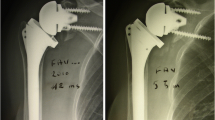

The concept of the reverse prosthesis developed by Grammont and Baulot [16] affords reasonable functional outcome in a rotator-cuff–deficient shoulder. Biomechanical [9, 10] and clinical studies [4, 5, 7, 28, 33, 35, 36] show the reverse prosthesis results in more powerful abduction of the shoulder despite complete loss of rotator cuff function. However, bony wear or remodeling (scapular notching) remains a common radiographic finding at early and late followups [4, 5, 23, 32, 33, 36]. The notch is consistently situated at the inferior pole of the scapular neck (Fig. 1) and is believed to be a source of mechanical failure [4, 5, 27, 32, 36]. Notching occurs in at least 50% of the cases with an increasing size and incidence at longer-term followup [4, 7, 32, 33, 35]. Notching negatively influences not only the mechanical outcome, but also the clinical outcome [32].